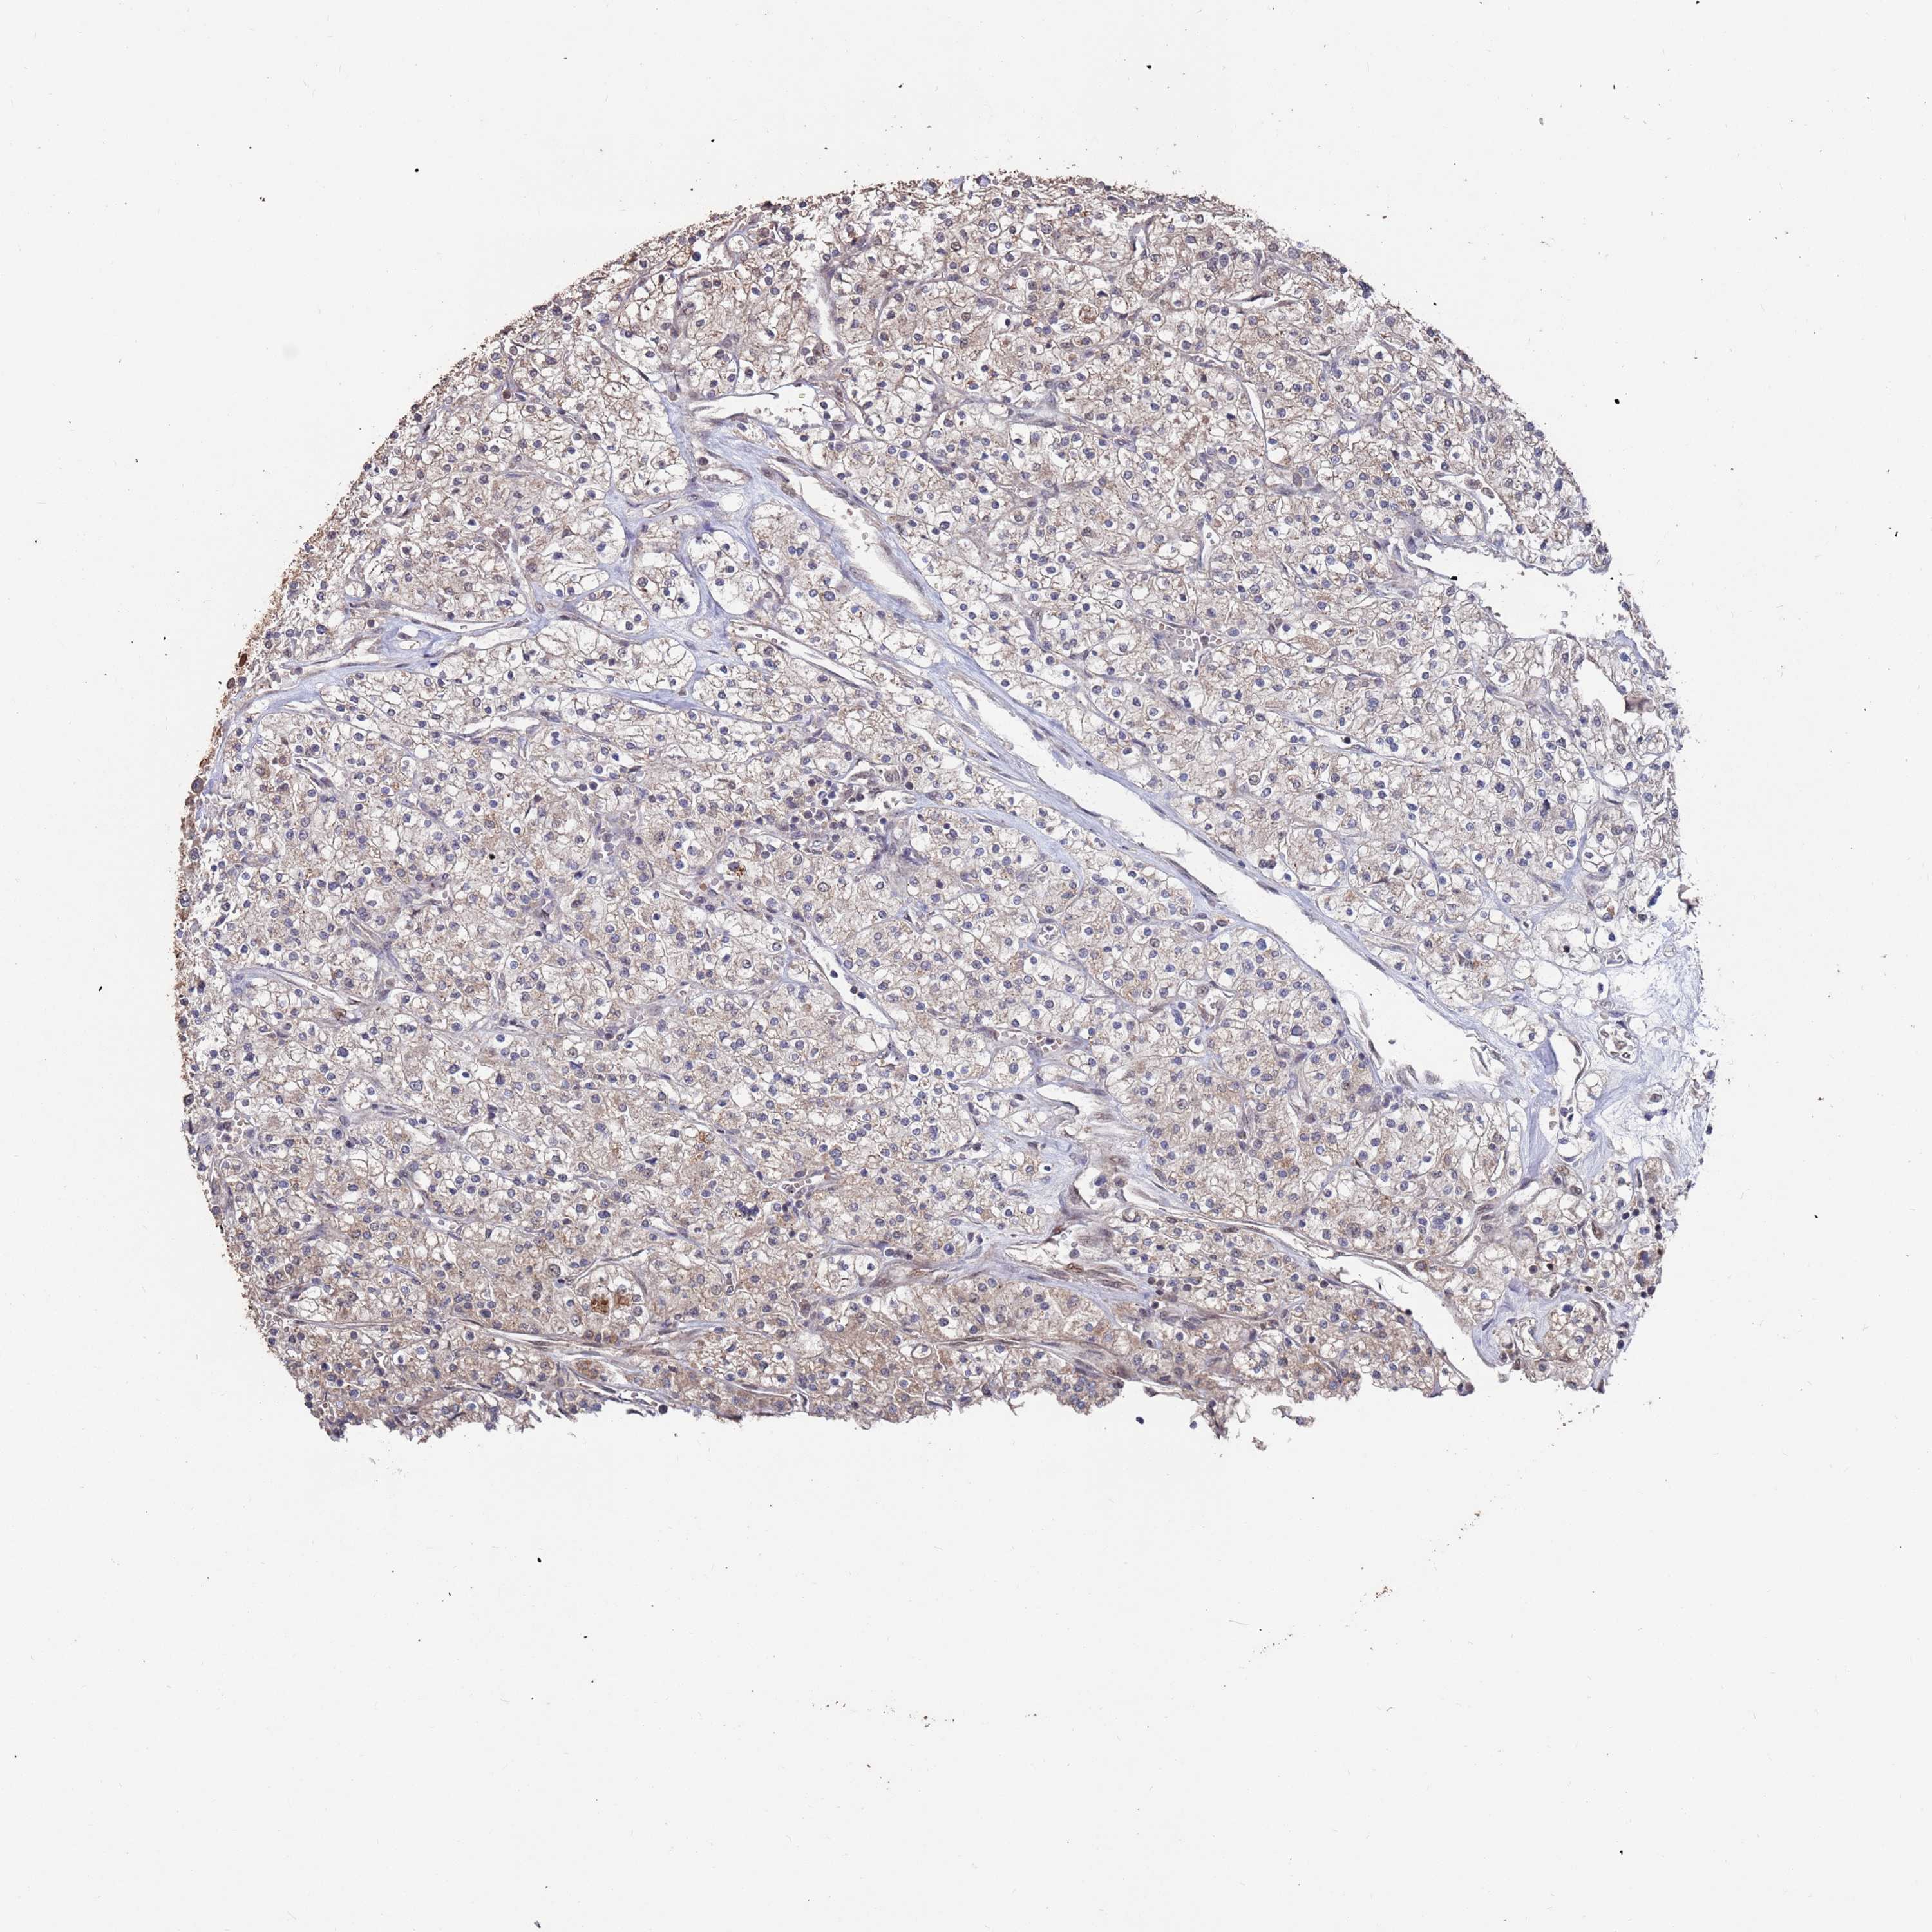

KIDNEY RENAL CLEAR CELL CARCINOMA (TCGA) - Interactive survival scatter ploti

The Survival Scatter plot shows the clinical status (i.e. dead or alive) for all individuals in the patient cohort, based on the same data that underlies the corresponding Kaplan-Meier plots. Patients that are alive at last time for follow-up are shown in blue and patients who have died during the study are shown in red.

The x-axis shows the expression levels (FPKM) of the investigated gene in the tumor tissue at the time of diagnosis. The y-axis shows the follow-up time after diagnosis (years). Both axes are complimented with kernel density curves demonstrating the data density over the axes. The top density plot shows the expression levels (FPKM) distribution among dead (red) and alive patients (blue). The right density plot shows the data density of the survived years of dead patients with high and low expression levels respectively, stratified using the cutoff indicated by the vertical dashed line through the Survival Scatter plot. This cutoff is automatically defined based on the FPKM cutoff that minimizes the p-score. The cutoff can be changed by dragging the vertical line or by entering a cutoff value in the square labeled "Current cut-off".

Under the Survival Scatter plot the p-score landscape (black curve; left axis) is shown together with dead median separation (red curve; right axis). Dead median separation is the difference in median mRNA expression between patients who have died with high and low expression, respectively. It is calculated as follows: median FPKM expression of dead patients with high expression - median FPKM expression of dead patients with low expression. This is intended to aid the user in visually exploring custom cutoffs and the associated p-scores and dead median separation.

Individual patient data is displayed and can be filtered by clicking on one or more of the category buttons on the top of the page. Categories describing expression level and patient information include: high, low, alive, dead, female, male and tumor stages. The scale of the x-axis can be toggled between linear and log-scale by clicking on the "x log" button. Mouse-over function shows TCGA ID, patient information and mRNA expression (FPKM) for each patient.

& Survival analysisi

Kaplan-Meier plots summarize results from analysis of correlation between mRNA expression level and patient survival. Patients were divided based on level of expression into one of the two groups "low" (under cut off) or "high" (over cut off). X-axis shows time for survival (years) and y-axis shows the probability of survival, where 1.0 corresponds to 100 percent.

PRR7 is not prognostic in Kidney Renal Clear Cell Carcinoma (TCGA)

Best expression cut offi

Based on the FPKM value of each gene, patients were classified into two groups and association between prognosis (survival) and gene expression (FPKM) was examined. The best expression cut-off refers the FPKM value that yields maximal difference with regard to survival between the two groups at the lowest log-rank P-value. Best expression cut-off was selected based on survival analysis .

When clicking on this number, the vertical dashed line indicating cut-off, the interactive survival plot, and the Kaplan-Meier curve will be adjusted to show results based on the best expression cut-off.

: 4.14

P scorei

Log-rank P value for Kaplan-Meier plot showing results from analysis of correlation between mRNA expression level and patient survival.

N/A

TCGA RNA samplesi

RNA-seq data is reported as average FPKM (number Fragments Per Kilobase of exon per Million reads), generated by the The Cancer Genome Atlas (TCGA) .

Normal distribution across the dataset is visualized with box plots, shown as median and 25th and 75th percentiles. Points are displayed as outliers if they are above or below 1.5 times the interquartile range. FPKM values of the individual samples are presented next to the box plot.

Average pTPM 3.4

Number of samples 521